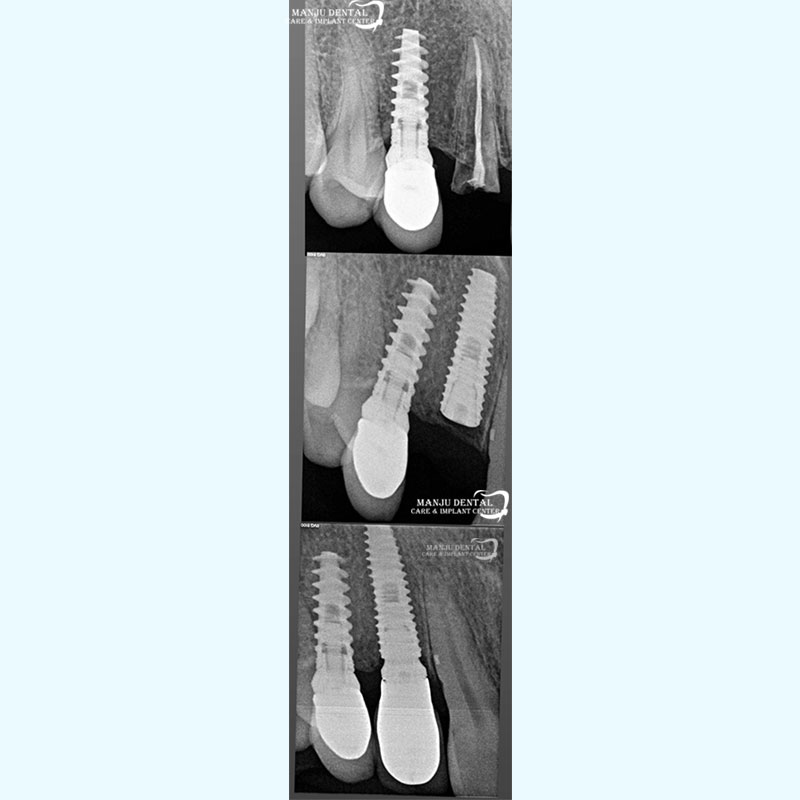

Precise Implant Placement For Long Term Stability And Natural Esthetics